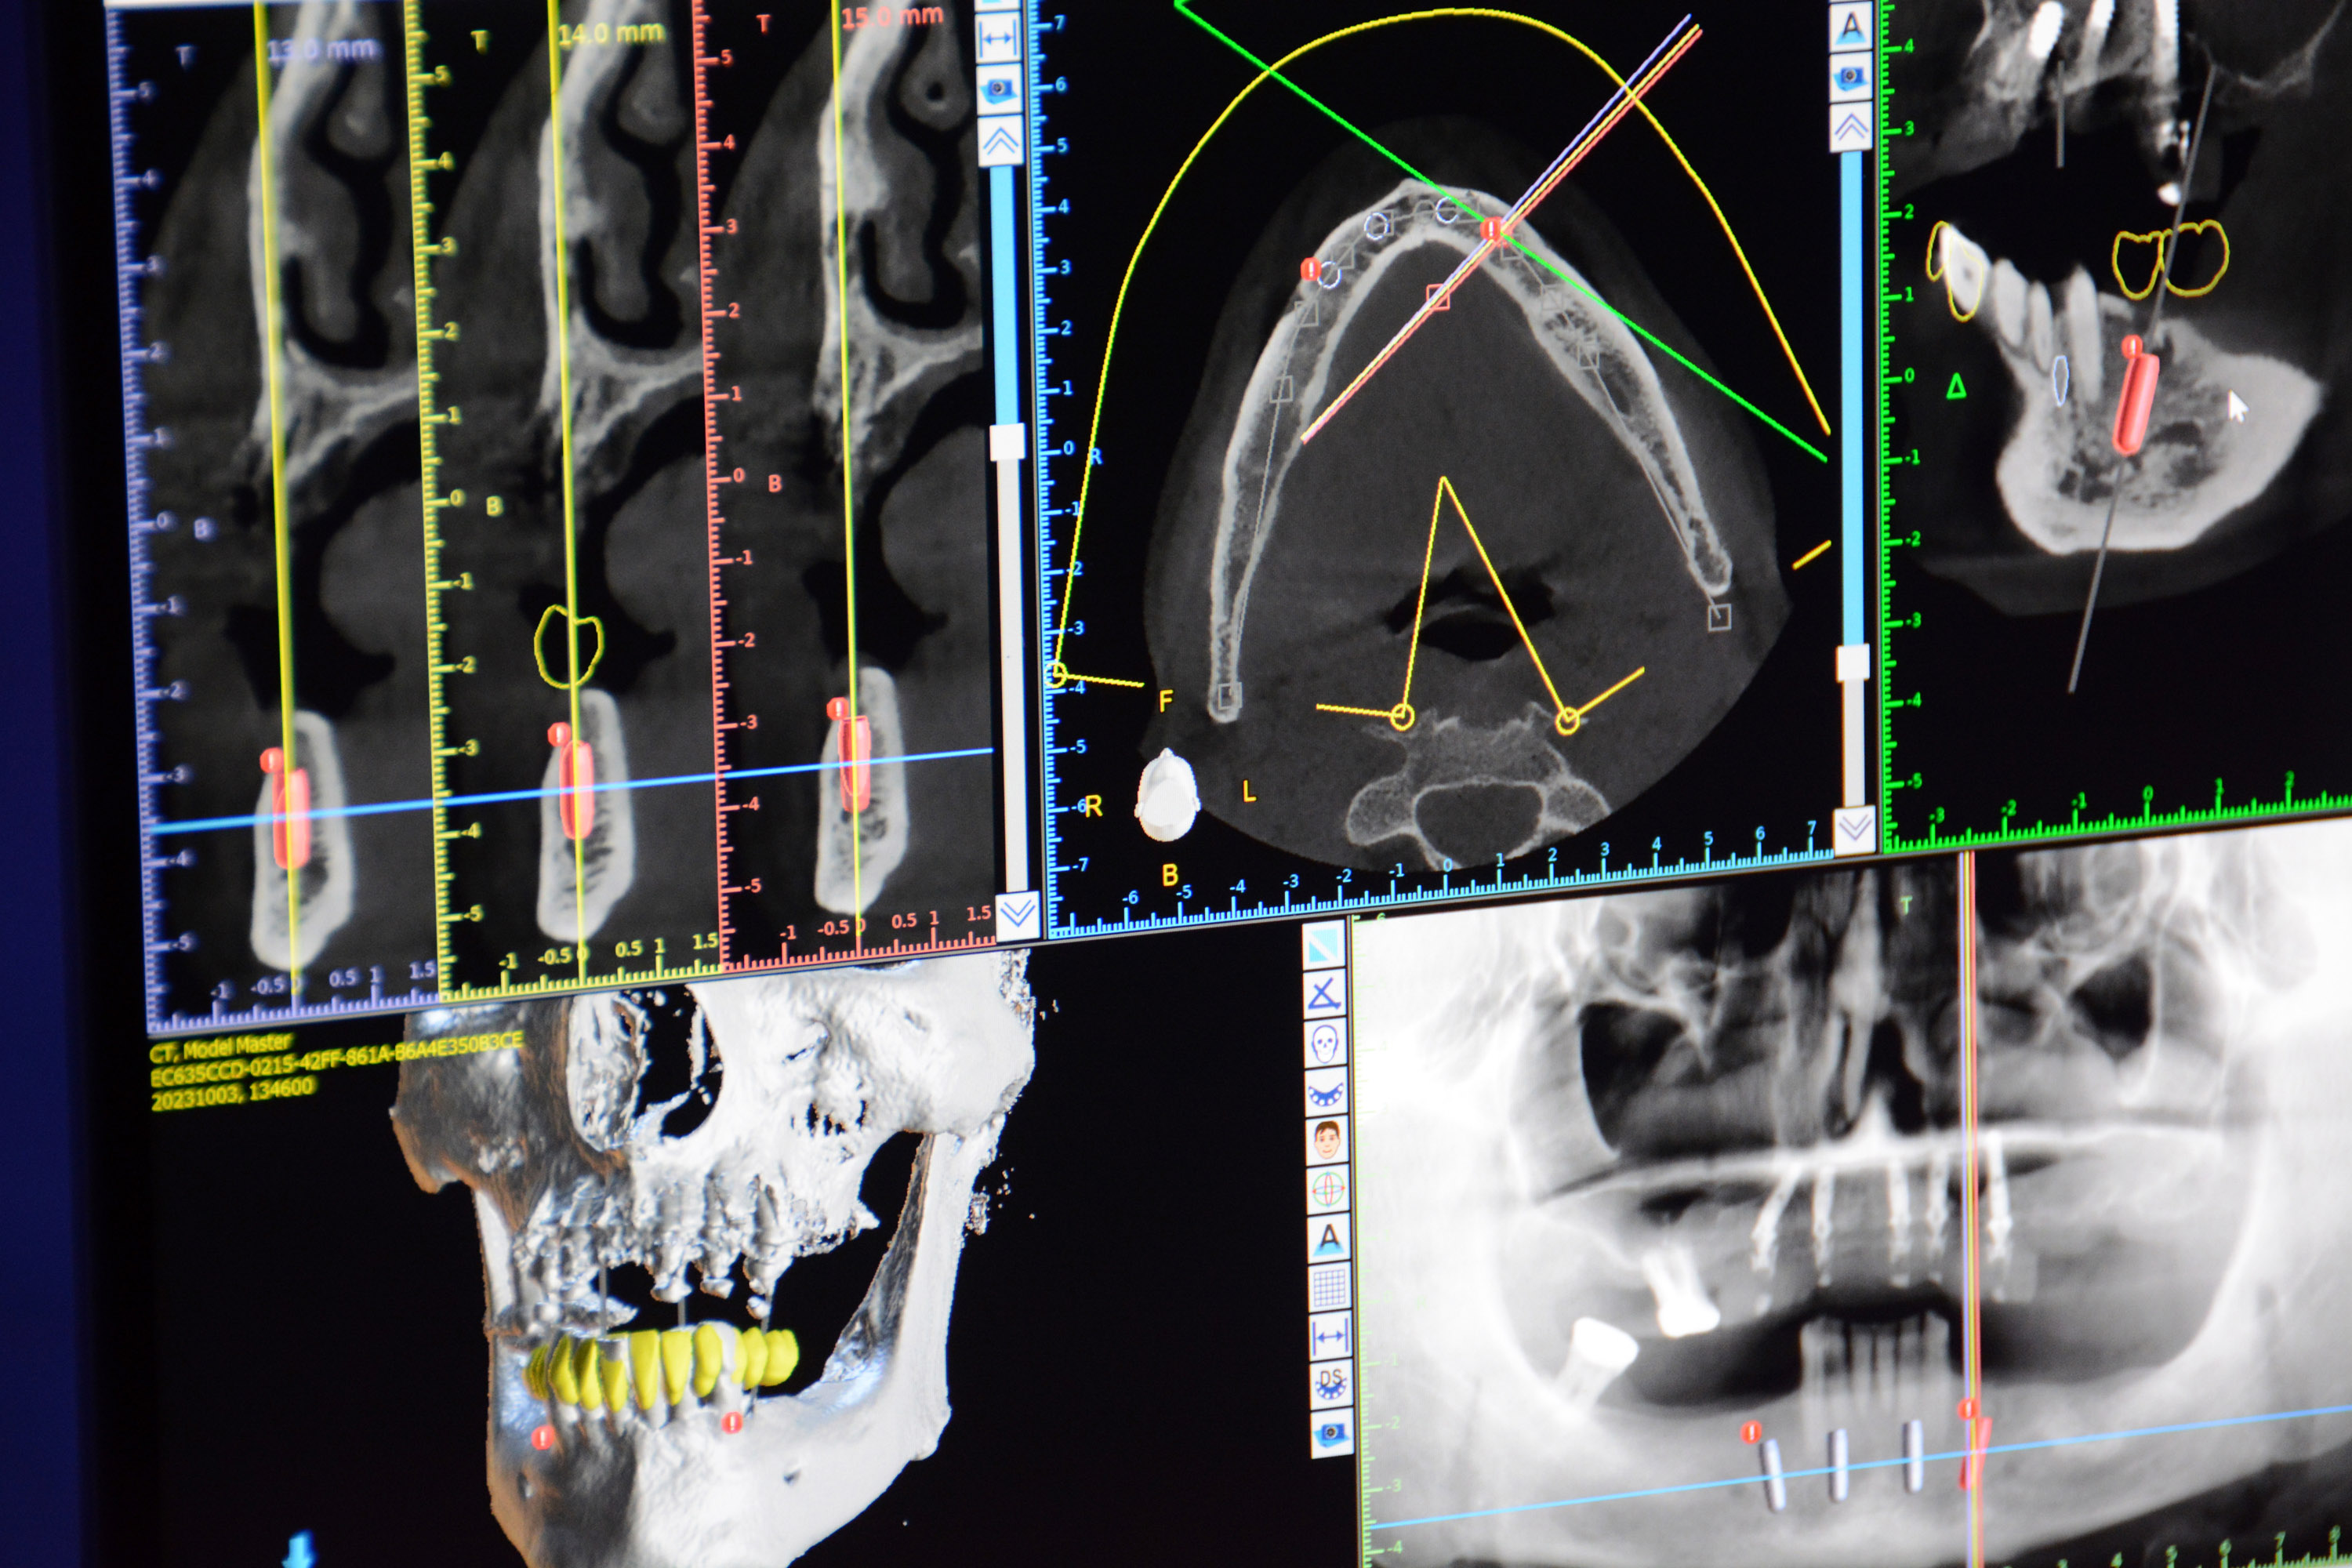

W piątek rozpoczęły się specjalistyczne wykłady dotyczące projektowania i wykorzystywania szablonów chirurgicznych w praktyce. Lekarze-dentyści dowiedzieli się, jak prawidłowo projektować wirtualnie pozycję implantu w przypadku pojedynczego zęba lub braków wielozębowych, bezzębia, a także na temat wskazań klinicznych i radiologicznych do zastosowania chirurgii nawigowanej.

Dr n. med. Adam Nowicki omówił rodzaje szablonów chirurgicznych. zaprojektował i wydrukował wraz z lekarzami szablon, niezbędny do przeprowadzenia sobotniego zabiegu.

W sobotę lekarze wysłuchali prezentacji dotyczącej kasety chirurgicznej do nawigacji i zastosowania wcześniej wydrukowanych szablonów.